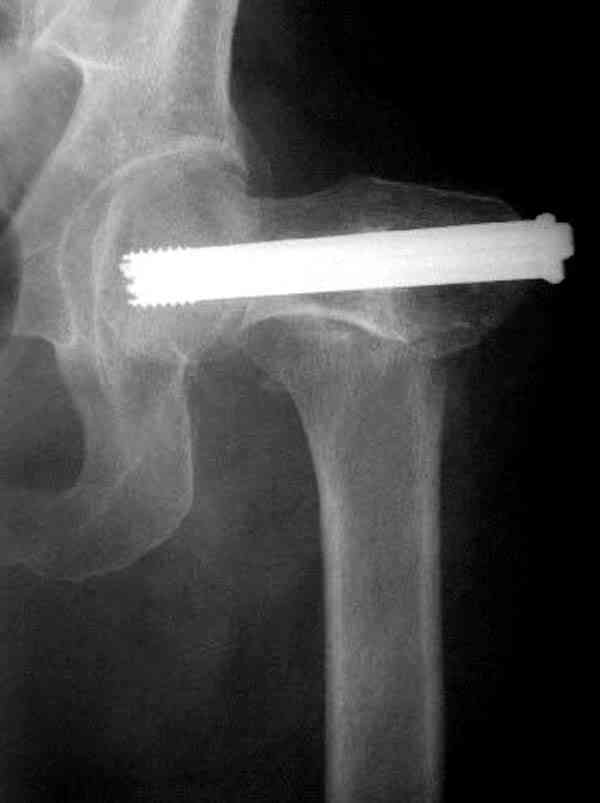

Здесь случай перелома из-за ослабления латерального кортекса через 3 недели после операции на шейке. Шурупы были установлены под большим углом, слабый латеральный кортекс не выдержал нагрузку.